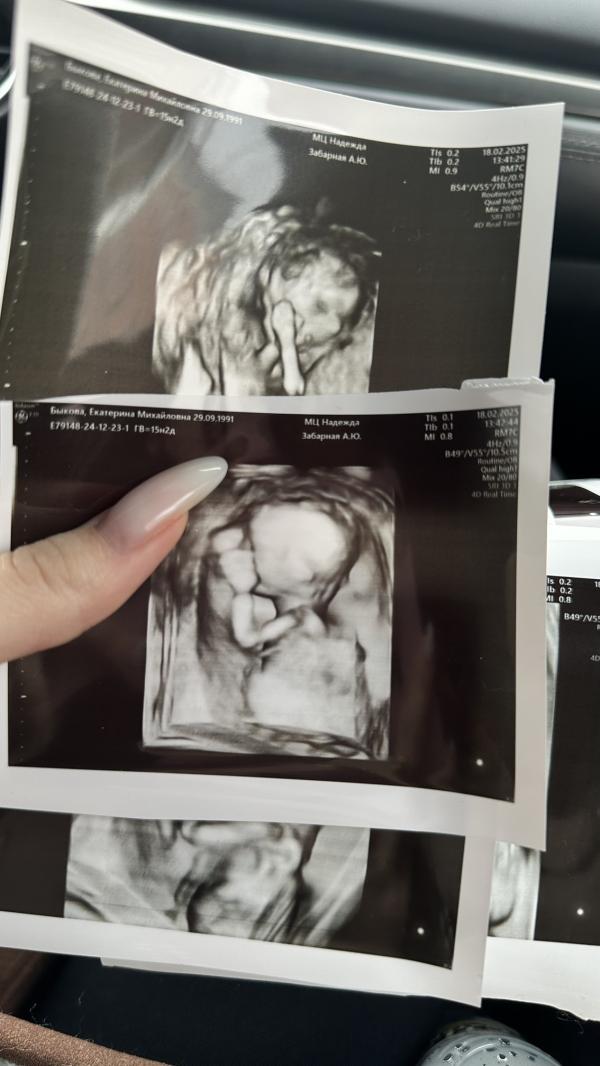

Сходила на узи))) какие же худенькие малыши на этом сроке (15,2) оказывается после 26 недель только они начинают обрастать жирком

Сейчас похож на инопланетяшку ❤️❤️❤️ зато полностью соответствует сроку, абсолютно здоровый, весит целых 139 грамм

Единственное к встрече был малыш не готов 😅 спал, да еще и повернуты спиной))) еле еле чуть перевернули, но не особо успешно, зато с уверенностью могу сказать, что позвоночник просто потрясающий 😅

Жду теперь 2-ого скрининга, так же предположили, что будет девочка 👧 скорее всего так и есть💞